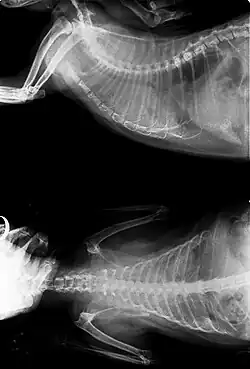

.jpg)